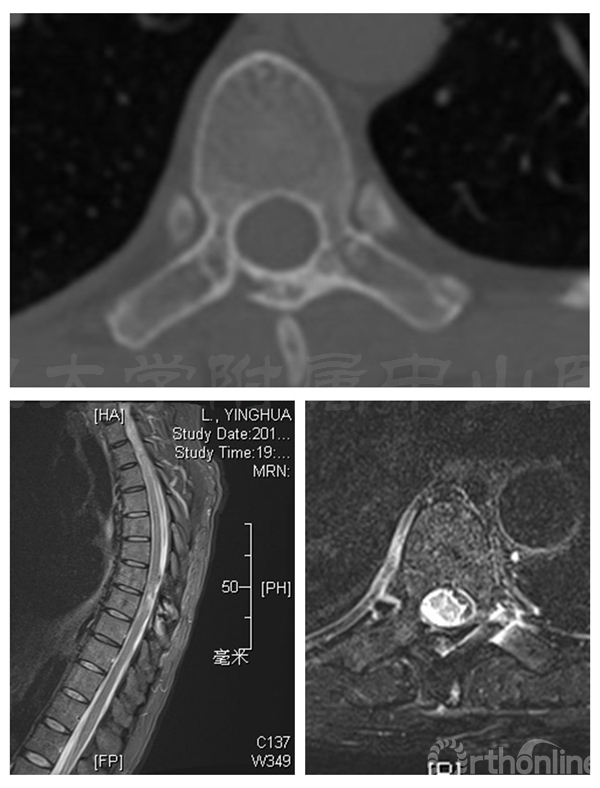

术前MRI:T7-8水平椎管内占位伴脊髓变性,脊膜瘤可能的大

术后半年CT显示两侧椎板截骨面均已骨性愈合,椎管体积无减少。MRI显示椎管内脊膜瘤无复发